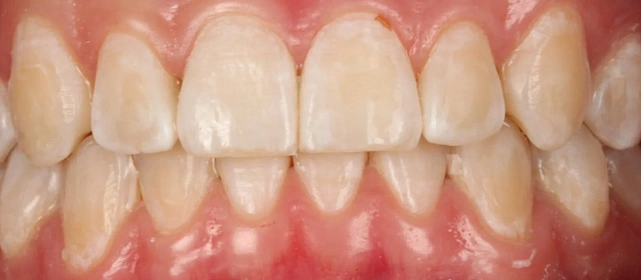

Зубы выровнены, смыкание нормализовано. Установлены несъёмные ретейнеры на обе челюсти. Пациент направлен к ортопеду.

Решение: Поставили элайнеры Invisalign на обе челюсти. Лечение заняло 4 года — случай потребовал нескольких этапов коррекции, каждый из которых последовательно приближал зубы к нужному положению. Капы менялись каждые 1–2 недели, контрольные визиты — для отслеживания прогресса и выдачи новых наборов. Зубы встали на место, смыкание пришло в норму. Зафиксировали ретейнеры на обе челюсти, пациент направлен к ортопеду для завершающего этапа.

Случай потребовал нескольких последовательных этапов коррекции. Invisalign позволяет дозаказывать капы в рамках лечения, и здесь это понадобилось — каждый следующий этап доводил положение зубов точнее. Результат достигнут, прикус стабилен, ретейнеры на месте. Пациента направила к ортопеду.